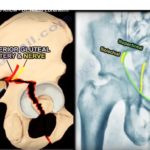

Posterior wall fractures of the Acetabulum

Courtesy: Prof Nabil Ebraheim, University of Toledo, Ohio, USA